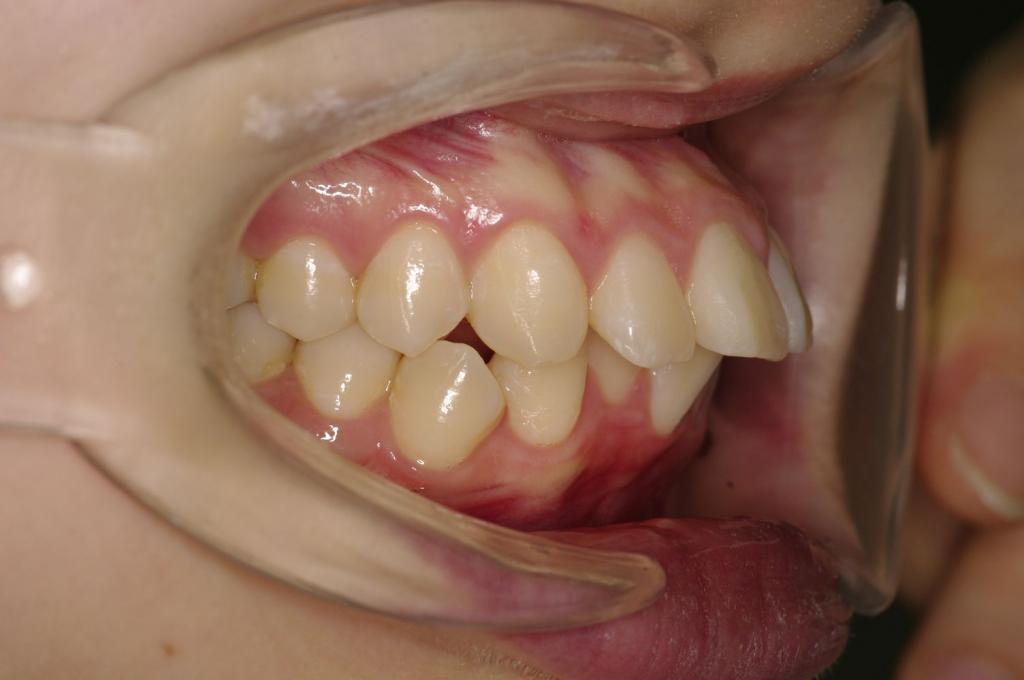

前歯、出っ歯・開咬の矯正治療

(治療期間、治療前後写真、治療方法、費用)WORKS